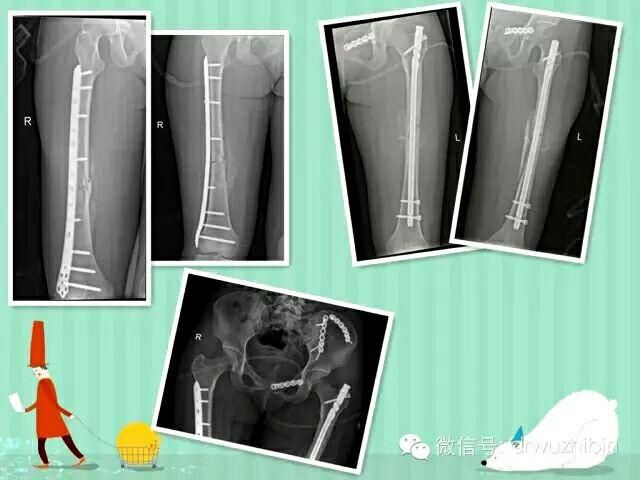

多發性創傷 永遠的挑戰2016-03-07

随着車禍、高處墜傷、地質災害等事件的逐步增多,多發性創傷、多發性骨折的患者也逐漸增多,此類病人損傷嚴重,緻死率、緻殘率比較高,對任何骨科團隊都是一個很大的挑戰。

康美醫院充分發揮整個外科團隊的協調作用,按照保命-保肢-保關節-保功能的治療原則,準确評估病情,制定合理治[ 查看詳細 ]